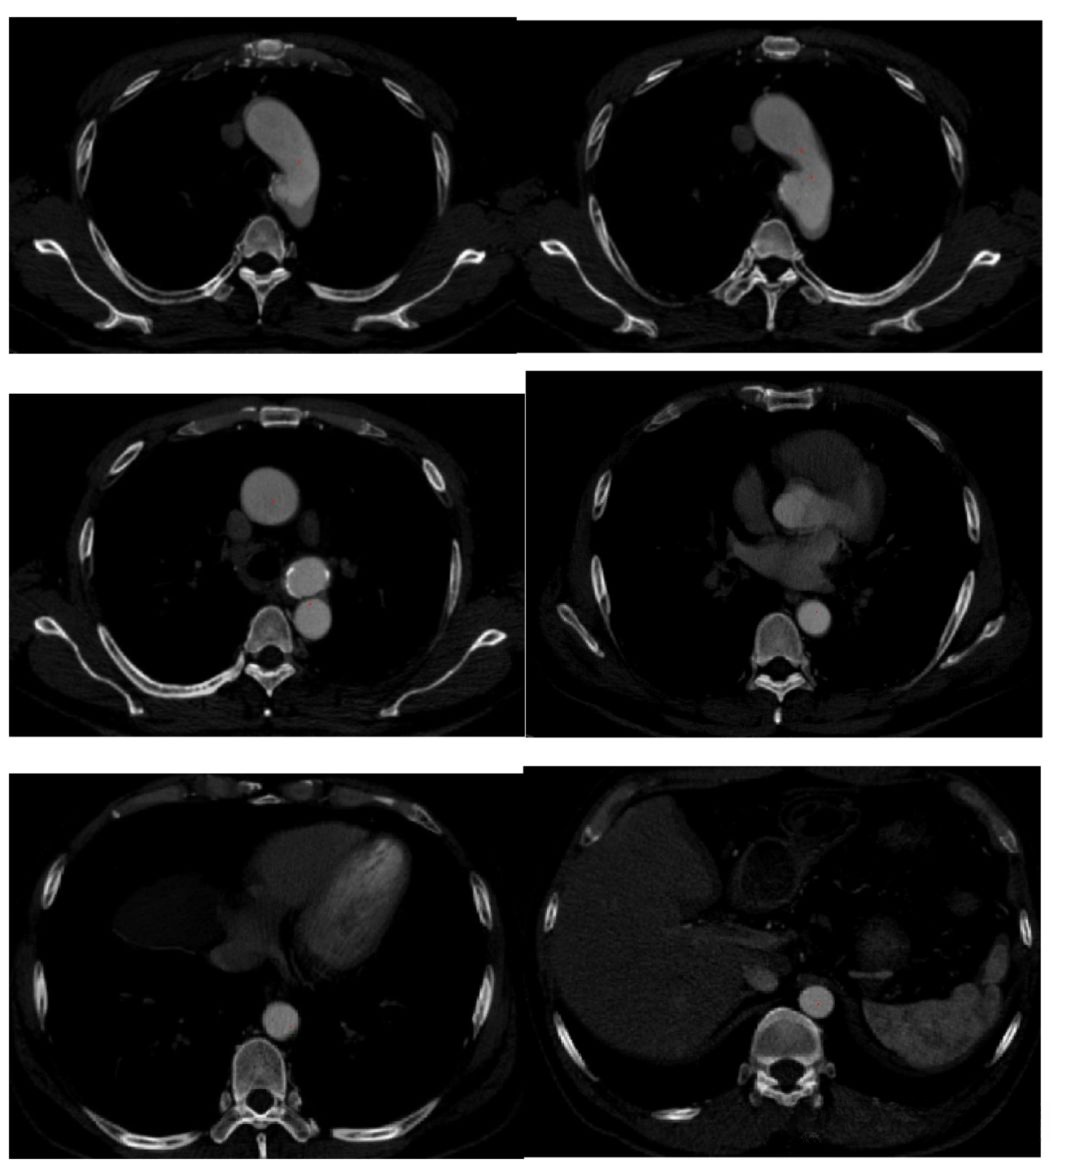

3、最小路径提取效果(2D与3D) 在DSA血管系统与CTA血管系统中分别进行了验证;其中图中显示的是血管原始图像;这些红色标记点即代表了最小路径提取的结果。